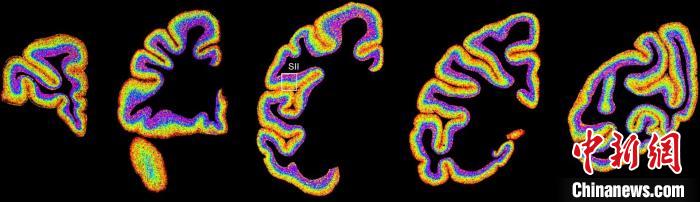

圖為不同類型細胞在獼猴大腦上的分布切片。 中國科學院腦科學與智能技術卓越創新中心 供圖

李澄宇說,科研人員做的事情好似“查戶口”,也就是搞明白猴腦里有哪些細胞、這些細胞在哪些位置。搞明白這些就形成了一個大的數據集,科研團隊挖掘這個數據集,發現了很多有意思的現象:比如,興奮性神經元、抑制性神經元以及非神經元在大腦皮層中的分布呈現明顯的特異性,也就是不同細胞“住”哪,有一定規律。